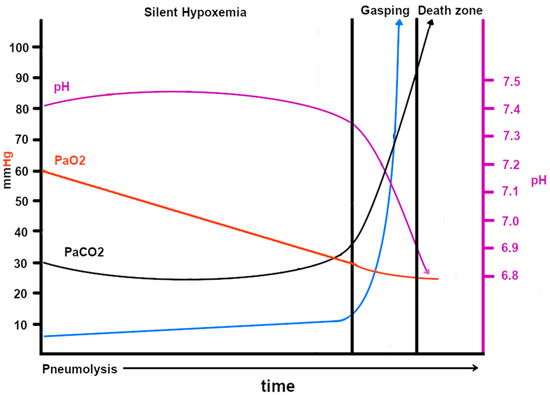

Figure 7.

This graph, developed by both Zubieta authors, shows the probable blood gases, acid–base, ventilation, and hypoxemia evolution in COVID-19 disease at sea level. Note that the pH scale is on the right and the PaO2, PaCO2 and ventilation scales are on the left. The CT scan images (courtesy of Centro de Estudios Tomográficos CET La Paz, Bolivia) show how, as the disease spreads throughout the lungs, the gas-exchange compromise increases, thereby reducing the oxygen transport through the alveolar–capillary membrane. The green, black, and yellow dots represent actual blood gases obtained from https://www.youtube.com/watch?v=_KMLW8eO0q0 (accessed on 28 December 2025) by Dr. Shiv Kumar Singh. The black and red dots are from [39].

COVID-19 patients often show a predominance of pneumolysis in the lower lobes of both lungs. The probable explanation may relate to aerodynamics and lung elasticity, which initially respond by distending the lower lobes on inhalation due to diaphragmatic contraction and the direct orientation of the main bronchi, thereby directing SARS-CoV-2 to the base of the lungs. COVID-19 lung injury involves direct viral epithelial cell damage and thrombotic and inflammatory reactions. There are differences between ARDS and COVID-19 lung injury in aspects of aeration distribution, perfusion, and pulmonary vascular responses [84]. It has been established that angiotensin-converting enzyme 2 (ACE-2) is the cellular receptor for severe acute respiratory syndrome–coronavirus (SARS-CoV) and the new coronavirus (SARS-CoV-2) [85]. SARS-CoV-2 enters type 2 pneumocytes [86], and since these cells are next to type 1 pneumocytes and sustain them, they are destroyed, and the whole alveolar structure is seriously compromised, as evidenced in several studies. The possible pathophysiological responses have been described in a paper entitled “Pneumolysis and Silent Hypoxemia” [18]. Figure 7 shows the pathophysiologic changes in COVID-19. Some newspaper interviews and publications in a local bulletin in La Paz, Bolivia, have informed the public about this new terminology and its implications [28].

However, as the disease progresses, all three hypoxia-producing conditions are present (diffusion, ventilation/perfusion inequality, and, above all, shunts), and it is for this reason that supplementary oxygen is unable to raise the SpO2 to normal levels (98% at sea level and 90% at 3500 m of altitude). Carbon dioxide (20 times more diffusible than oxygen) can still be adequately ventilated and expelled despite the significant reduction in the oxygen exchange surface (Figure 6). However, when the lung exchange surface is seriously compromised, the lung is unable to eliminate excess carbon dioxide [87], and this is when gasping occurs (Figure 6). It is essential to observe that the SpO2 falls linearly as the expansion of the pneumocyte invasion of SARS-CoV-2 evolves. We initially thought it would be a curve; however, based on actual blood gas data, it was concluded that it was most probably linear.

Originally, we also observed that there were not many changes in pH or PaCO2 in the “silent hypoxemia” phase [18], with mild hyperventilation as also described by [39]. The latter points out fundamental aspects; however, the whole picture is incomplete. In our experience, high-altitude residents at 3600 m (as at any altitude) actually live with a permanent “silent hypoxemia”. With this experience, we are able to propose the explanation of the baffling “silent hypoxemia” in COVID-19. It is for this reason that we postulate that during acute hypoxemia with the impossibility of raising PaO2 and SpO2, a fundamental solution in order to save lives would be to use of extracorporeal oxygenation [18] and the administration of erythropoietin.

The pathophysiology of COVID-19 at high altitude is shown in Figure 8, where the starting PaO2 is 60 mmHg at 3500 m. The descent to critical hypoxia is not as steep as at sea level. This could help explain the lower incidence of COVID-19-related deaths at high altitudes.

This graph shows the probable blood gases, acid–base, ventilation, and hypoxemia evolution in COVID-19 disease at 3500 m (12,000 ft) of altitude, where the normal PaO2 is 60 mmHg and the normal SpO2 is 88–92%. Notice that the gradual PaO2 decrease slope is much lower and is, hence, related to a higher tolerance to hypoxia than at sea level (with a lower PaCO2 = 30 mmHg), which becomes an advantage for survival until immunity ensues. The death rates from COVID-19 are much lower at high altitudes than at sea level. The blue arrow is ventilation.